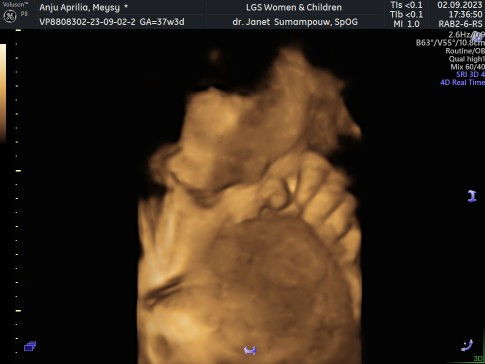

Alhamdulillah sudah lahir anak kedua ku. HPL 20 September, lahir 19 September dengan proses Cesar. Jenis kelamin bayi Laki-laki Lahir dengan berat 3.8kg Panjang Lahir 49cm Niatnya mau lahiran normal, tapi adek bayi kenceng terus ga mules mules, sudah keluar flek pun gamules sama sekali. Jadi tgl 18 saya USG ke dokter, dan langsung di kasih jadwal Cesar karena ternyata bayiku besar gak masuk panggul dan ketuban sudah lengket. Sempet deg degan tapi pas bayi sudah lahir sehat sudah sedikit lega. Tinggal proses recovery yang panjang karena ternyata lebih enak lahiran normal menurut ku (anak pertamaku lahir normal/pervaginam)🙂🙂#firstbaby